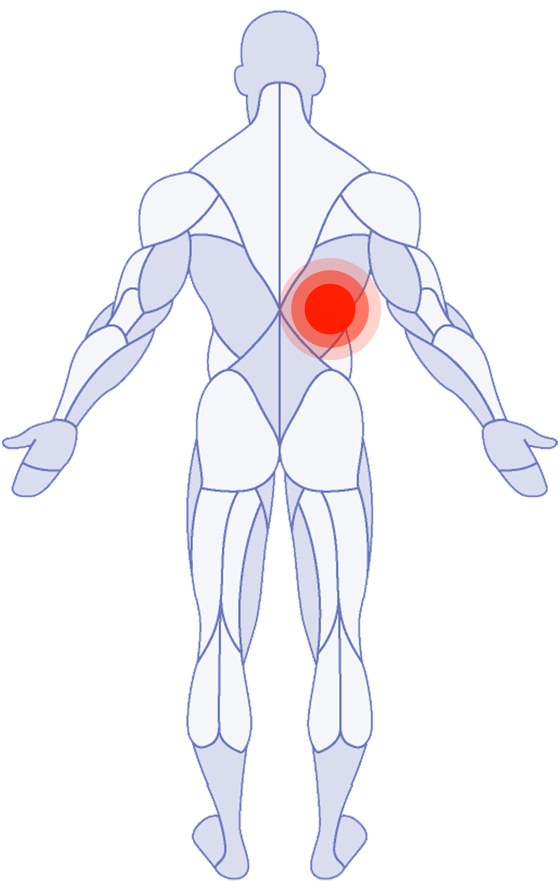

Where do you need attention?